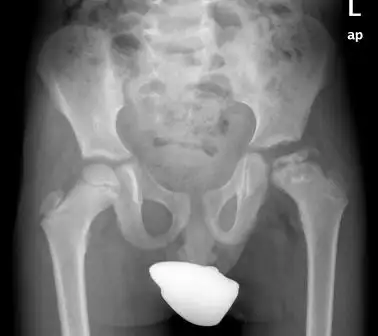

- Nẹp Chỉnh hình với chức năng CÂN BẰNG (bù) sự chênh lệch phát triển cho các trường hợp ngắn, lệch chiều dài chi. Bệnh nhân bị ảnh hưởng sự phát triển của cơ và cả sự phát triển không đều theo chiều dài của của xương; Nẹp chỉnh hình thường cần phải bù chiều dài một phần chân để tạo sự cân bằng khung chậu đối với chân bị ảnh hưởng chiều dài.